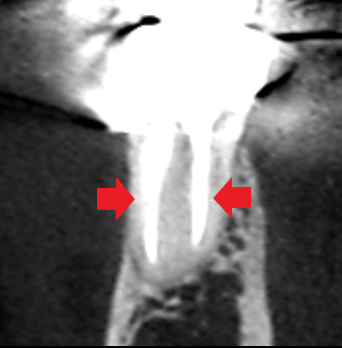

実際に「根管」の画像をご覧頂きましょう。歯の中にある黒い筋が根管です。